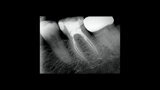

Treatment of the result of chronic activation of substance P